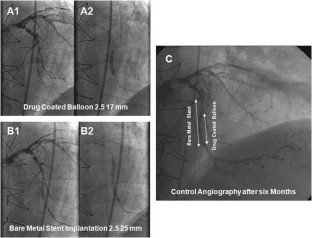

Eighty-two of 118 patients (70%) with a vessel diameter of 2.35 ± 0.19 mm were treated with the drug-coated balloon only, while 32 patients required additional stent deployment. The mean in-segment late lumen loss was 0.28 ± 0.53 mm. In patients treated with the drug-coated balloon only, the in-segment late lumen loss was 0.16 ± 0.38 mm. At 12 months, the rate of major adverse cardiac events was 15% which was primarily due to the need for target lesion revascularization in 14 patients (12%). In those with additional bare metal stent implantation geographical mismatch between coated-balloon dilatation and stent implantation was significantly associated with the occurrence of restenosis.

Fig. 1